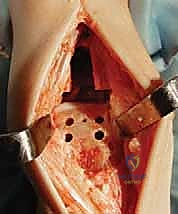

4. تركيب المفصل الصناعي (Implantation)

يتكون مفصل الكاحل الصناعي الحديث عادة من ثلاثة أجزاء:

* قطعة معدنية علوية: تُثبت في عظمة الظنبوب (الساق).

* قطعة معدنية سفلية: تُثبت في عظمة الكاحل.

* قطعة بلاستيكية (بولي إيثيلين عالي الكثافة): توضع بين القطعتين المعدنيتين لتنزلق بسلاسة وتمتص الصدمات، محاكيةً وظيفة الغضروف الطبيعي.

يتم تثبيت هذه الأجزاء بإحكام (إما عن طريق الضغط المباشر لتشجيع نمو العظم حولها، أو باستخدام أسمنت طبي خاص).